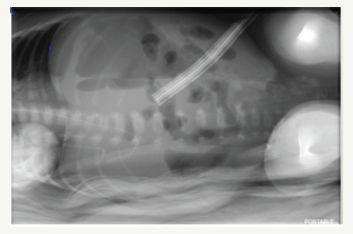

His abdominal distension was noted to gradually resolve and once he was noted to be hemodynamically stable along with improving platelet counts, normalized coagulation profile with declining CRP levels and sterile blood culture (Figure 4).

Figure 4:

Baby underwent laparotomy with resection and Anastomosis of his intestine and formation of ileostomy on (day 13 of life and 6 days following drain insertion).One perforation was noted at DJ junction and multiple perforations were noted proximal to ileocecal valve and approx. 15cms of bowel resection was performed followed by end to end anastomosis. The histopathology of the bowel specimen sent revealed Necrotizing Enterocolitis (Figure 5).